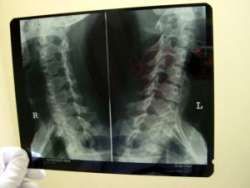

Lekári objavili nové ochorenie, spôsobuje dlhodobé bolesti chrbta

Dlhodobé bolesti chrbta môže spôsobovať aj ochorenie, ktoré lekári objavili u Slovákov iba prednedávnom. Ide o tzv. axiálnu spondylitídu, ktorá postihuje mladých ľudí v produktívnom veku do 40 rokov. "Základným príznakom ochorenia je bolesť chrbta pretrvávajúca viac ako tri mesiace. Aj preto sme si ešte pred niekoľkými rokmi mysleli, že ide o bežnú bolesť chrbta. Teraz sa však prišlo na to, že ide o úplne nové ochorenie, spojené so zmenami na chrbtici a v oblasti panvy," uviedol primár Národného ústavu reumatických chorôb Jozef Lukáč.